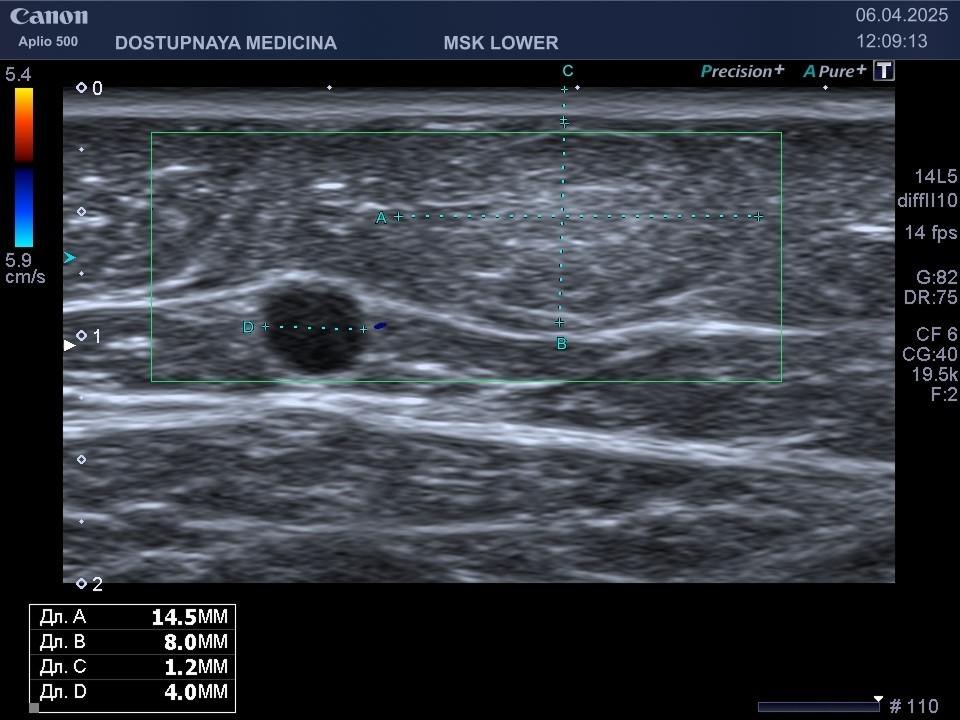

При ультразвуковом исследовании липома чаще всего выглядит, как гипоэхогенное образование овальной или округлой формы, мало отличающееся по своей эхоструктуре от окружающей её подкожной жировой клетчатки, без кровотока в режиме ЦДК. В описании заключения важно так же отметить прилежит ли близко опухоль к какому-либо кровеносному сосуду или нерву.